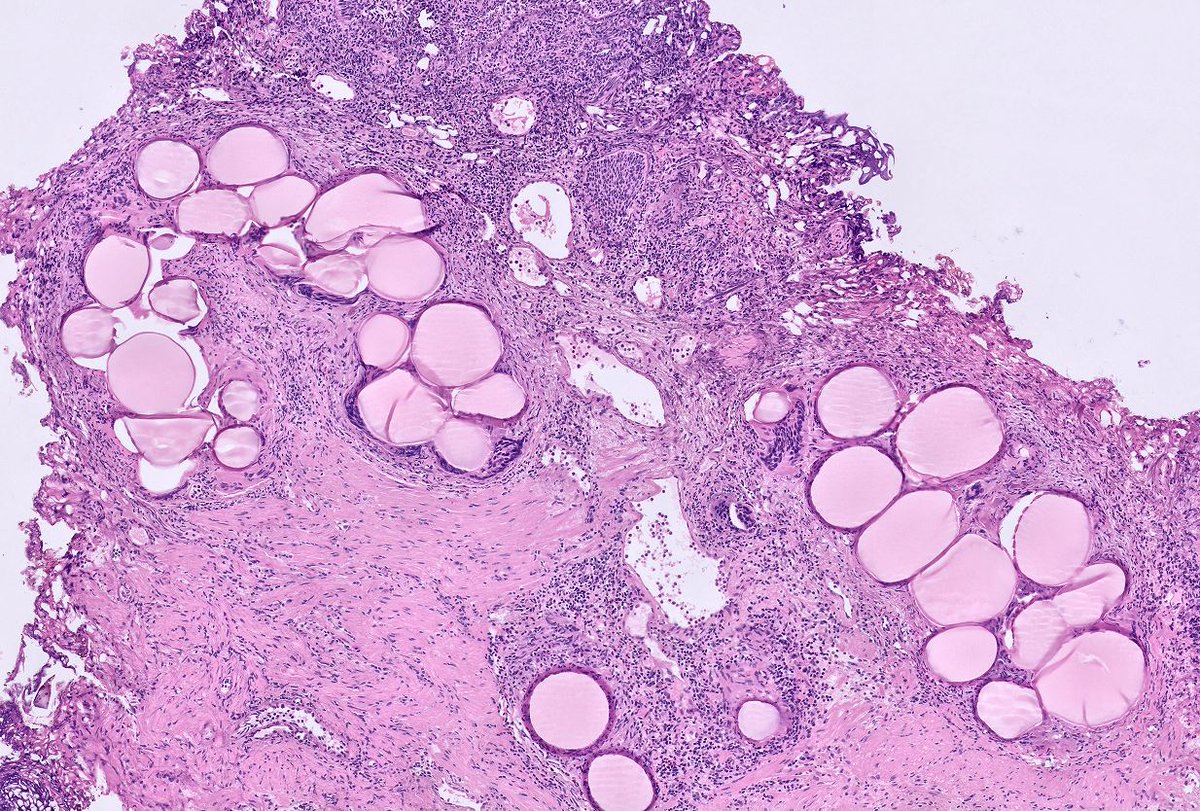

Any thoughts on this beautiful, elegant creature that "crawled" into the colonic mucosa and presented as polyp !! I have been googling it for ages and can't find a morphologic fit with any of the adult/ larval parasitic forms that I have ever encountered. Pt is asymptomatic.